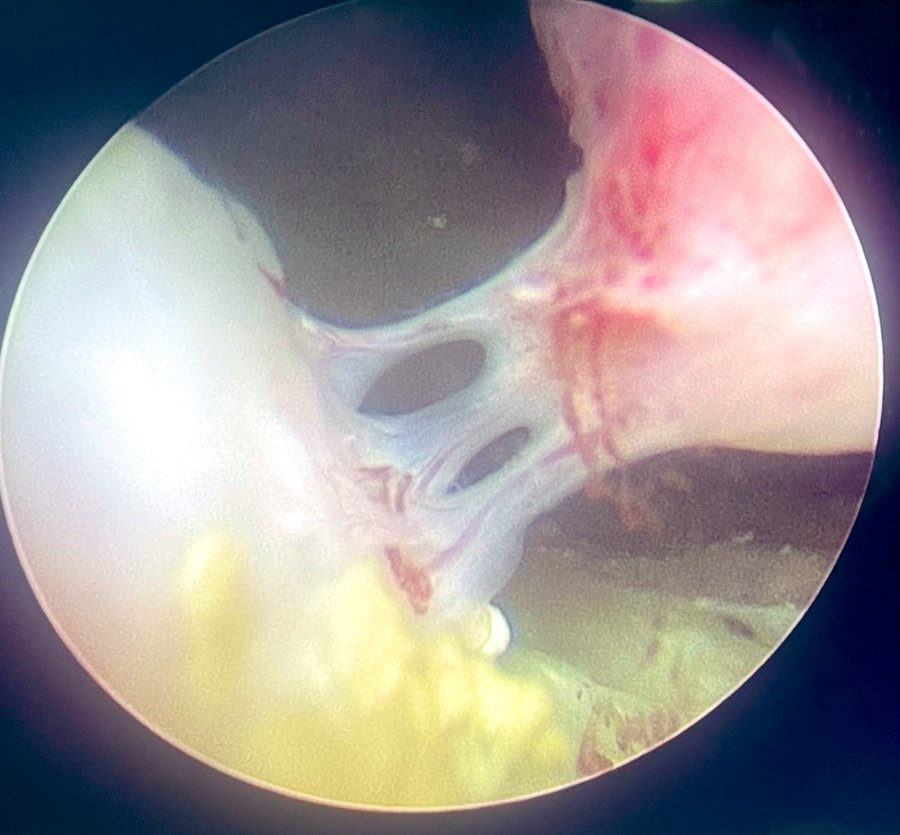

From the desk of Perry Xu, MD (@perryjxu): -Dr. Xu is seeing more patients post-aquablation with persistent gross hematuria and LUTS. -Here are some endoscopic images post-aquablation (6 months to a year ago). Most impressively, one patient had fused vessels across the aqua…

-Dr. Xu is seeing more patients post-aquablation with persistent gross hematuria and LUTS.

-Here are some endoscopic images post-aquablation (6 months to a year ago). Most impressively, one patient had fused vessels across the aqua…